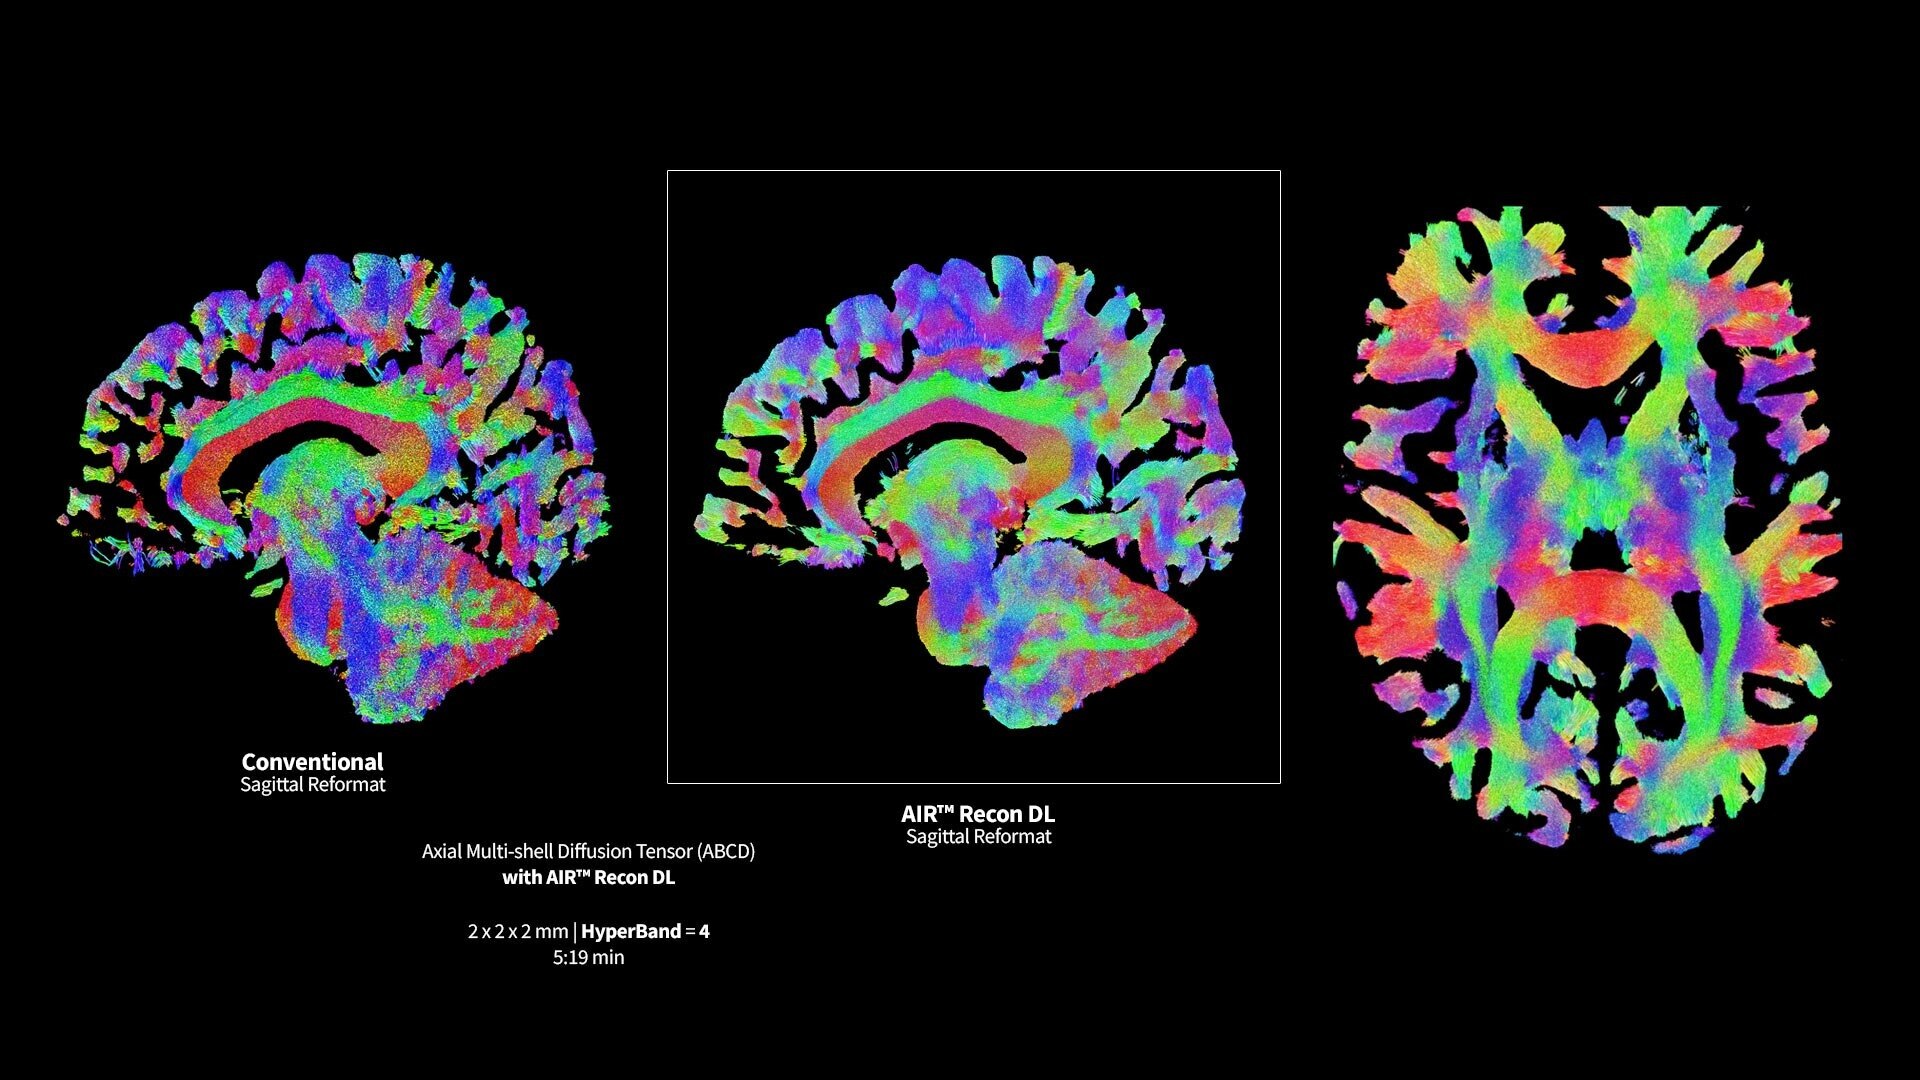

MR image reconstruction with AIR Recon DL

Evolve your MRI scanner's capabilities: experience exceptional image quality without compromising scan time.